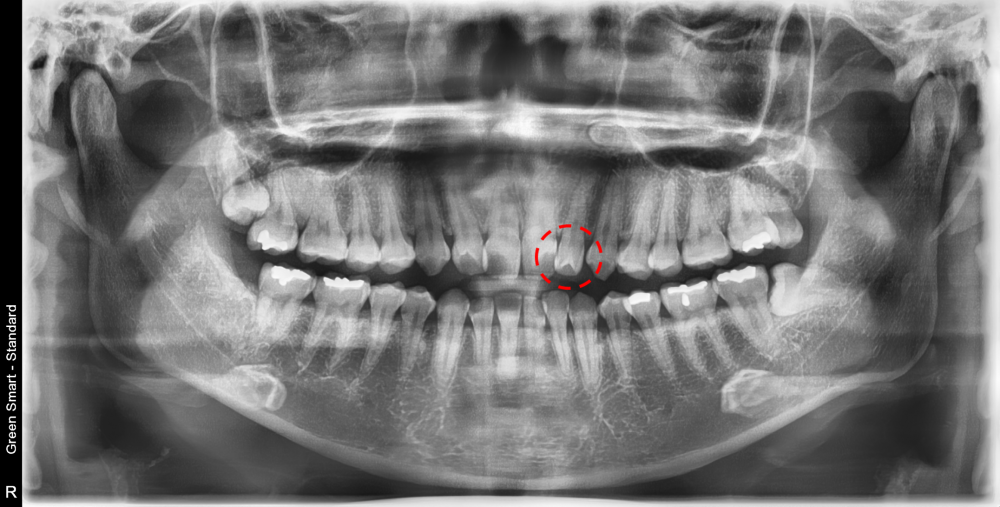

** 치내치는 겉으로 드러나는 경우도 있지만, 많은 경우 X-ray나 CT 촬영을 통해 발견됩니다.

✔ X-ray 상에서 치아 속에 하얗고 작은 치아가 하나 더 있는 것처럼 보임

✔ 치근단 염증이나 신경통증

치내치는 치수(신경)와의 연결이 복잡하므로, 단순 충치치료만으로는 문제가 해결되지 않는 경우가 있습니다.

약간의 충치가 진행된 상황이었으나, 다행히 깊이가 많이 깊지 않아서 간단한 레진 치료 후 교정 치료를 시작할 수 있었습니다.

따라서 교정 전에는 반드시 구강 내 검진, 파노라마 X-ray, 3D CT, 디지털 스캐너 등을 이용한 검사를 통해 치아 구조를 꼼꼼하게 확인하는 것이 중요합니다.